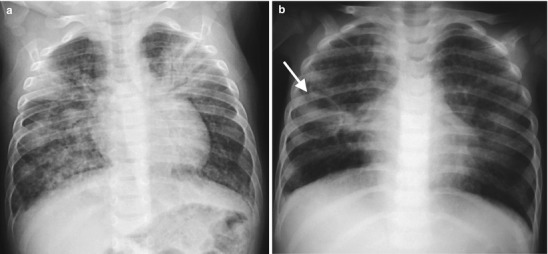

Fig. 13.18.

Primary TB disease. Chest radiographs of a 2-year-old girl with chronic cough and fever showing dense right middle lobe consolidation on the frontal view (a) and extensive lymphadenopathy (white arrows) on the lateral view (b)